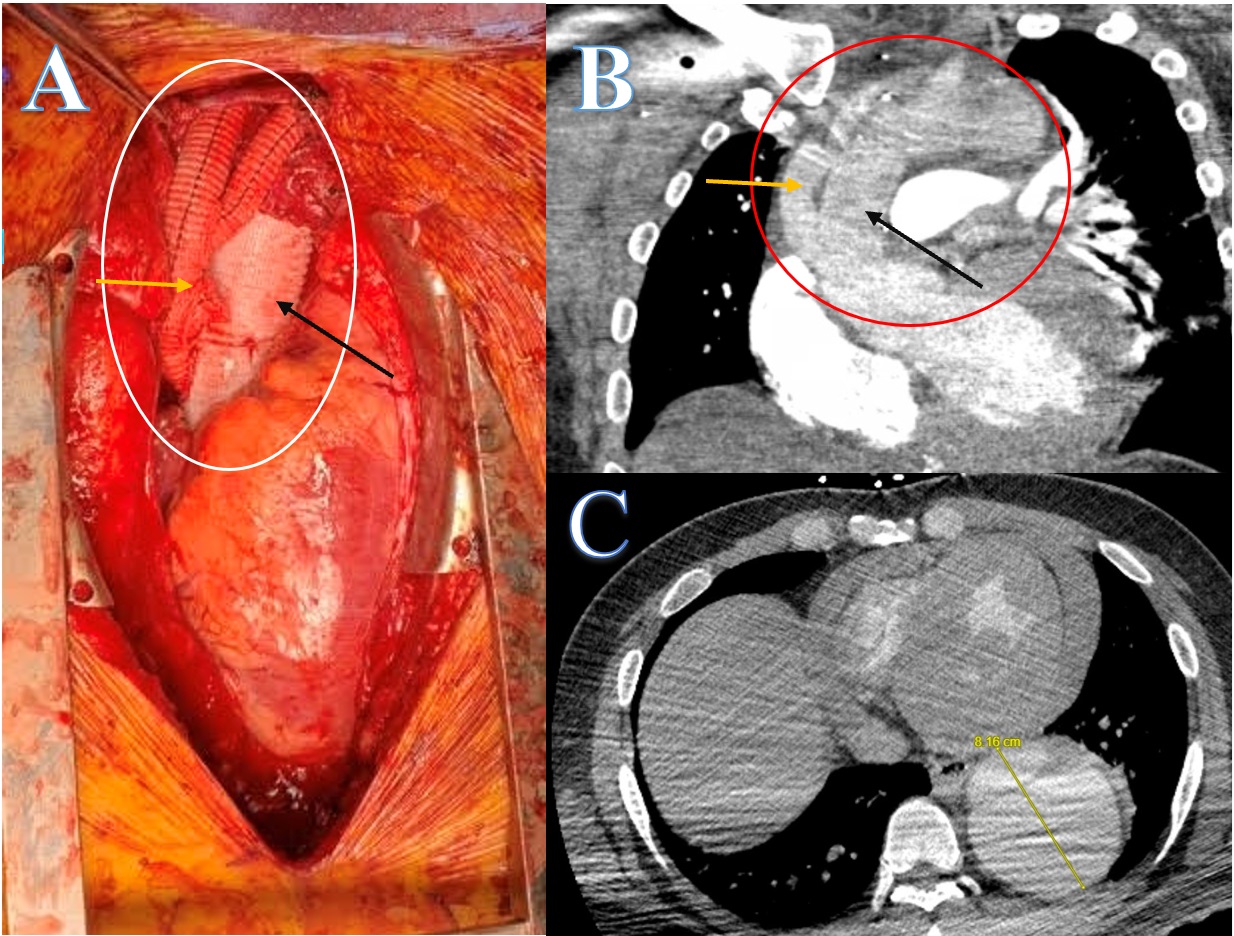

The patient underwent ascending aorta replacement with a 28-mm tube graft as well as debranching of the innominate artery and left carotid artery using a trifurcating graft connected to the medial side of the mid-ascending aorta just cranial to the sinotubular junction (Figure A and B). Residual dissection in the arch was noted but not addressed during the initial surgery with plans for repair of the arch and descending aorta within 3 months. There was no time to perform coronary evaluation prior to the emergency surgery; however, intraoperatively, significant coronary calcification of the left anterior descending artery was noted. The left ventricle had no wall motion abnormalities, and the patient recovered from the first surgery uneventfully.

Before the second surgery, coronary angiogram was required to address any coronary artery disease (CAD). Vascular access was limited due to the complex dissection of the descending aorta and the distal aortic arch (Figure C), necessitating a right radial artery approach.